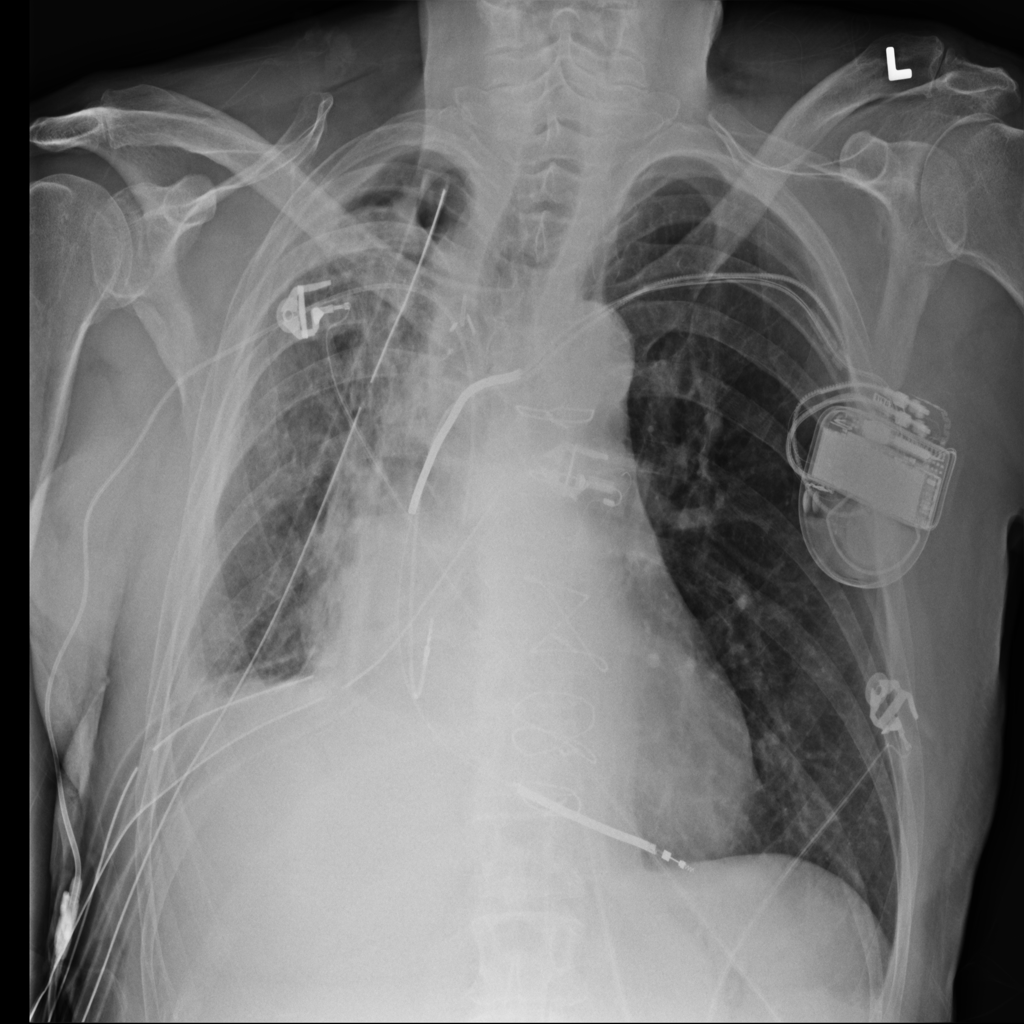

PAT-4639 · IMG-011Pneumothorax

PAT-4639 · IMG-011

AP